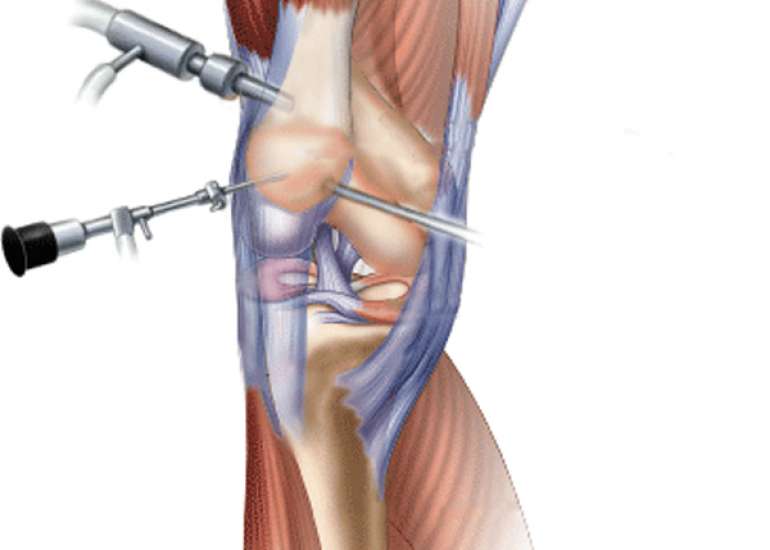

Director (Orthopaedics & Joint Replacement) & Head of Unit-1, Max Smart Super Speciality Hospital, Saket